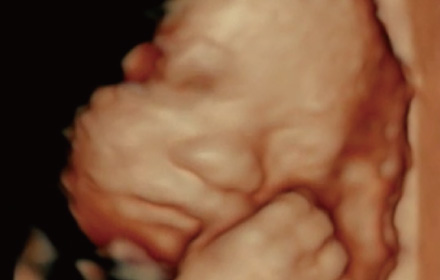

胎児4Dエコー

2D超音波(通常の健診での超音波)よりも、より胎児の体の細かな部位の抽出や立体感あふれる画像を表示できます。

赤ちゃんの手や足、あくびなどの可愛らしい動きもリアルタイムに表現できます。

- 胎児4Dエコーのみの利用も可能です。

- 料金は1回につき、4,000円です。

- 他院で健診を受けられている妊婦さまが胎児4Dエコーのみご利用いただくことも可能です。